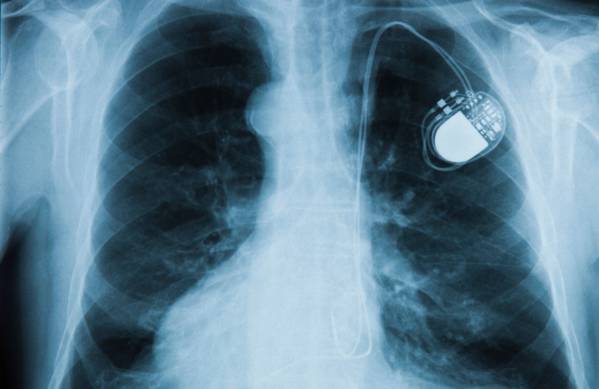

Scandale des implants défectueux

Les implants se multiplient dans nos corps, pour nous aider à vivre mieux. Leur évolution technique les rend toujours plus faciles à placer, au point de...